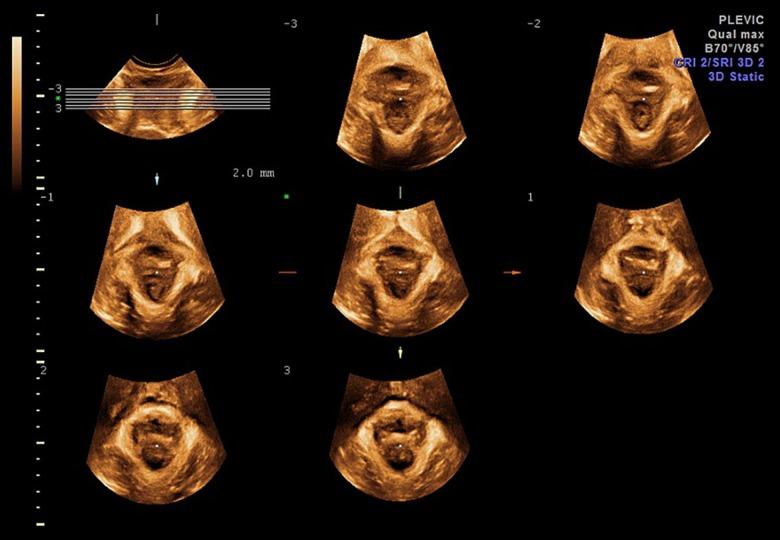

Correlation Between Delivery Mode and Pelvic Organ Prolapse Evaluated by Four-Dimensional Pelvic Floor Ultrasonography.

BACKGROUND This study explored symptoms and signs of pelvic organ prolapse (POP) evaluated by 4-dimensional pelvic floor ultrasonography and analyzed the relationship between delivery mode and POP. MATERIAL AND METHODS A total of 578 women who underwent 4-dimensional transperineal ultrasound were enrolled in this study. Obstetric history together with other clinical information were gathered from clinical questionnaires and gynecologists. Patients were thereafter classified into 4 groups: women with normal vaginal delivery, women with forceps delivery, women with cesarean, and nullipara women. We assessed symptoms and signs of POP among these 4 groups by use of 2 evaluation methods. The first method was clinical assessment applying International Continence Society (ICS) pelvic organ prolapse quantification (POP-Q). The second method was the use of ultrasonography in the quantification of anterior, middle, and posterior compartment prolapse. RESULTS Nulliparae women exhibited the lowest probability of POP (POP-Q: cystocele of 15.6%, uterine prolapse of 11.1%, rectocele of 20.0%; ultrasound exam: 6.7%, 8.9%, 13.3% in sequence), while women with forceps delivery had the highest probability of POP (POP-Q: 59.6%, 50.8%, 63.2% in sequence; ultrasound exam: 45.6%, 52.6%, 42.1% in sequence). Regarding the correlation between POP and delivery mode, the adjusted odds ratio was 2.40 (95%CI: 1.3014.590) and 3.20 (95%CI: 1.6516.121) in the normal vaginal delivery group and forceps group, respectively, compared with the cesarean group. CONCLUSIONS Four-dimensional pelvic floor ultrasonography can be used as a preferred method in evaluating POP. Regarding the relationship between delivery mode and POP, there is a significant correlation between vaginal delivery and POP.